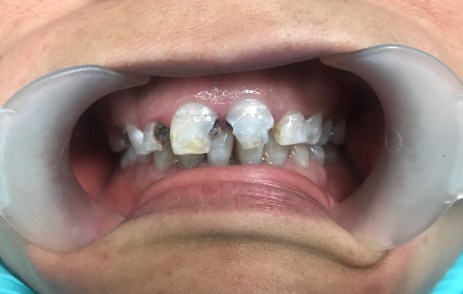

#7 MIFL, #8 MIFL, #9 MIDFL, #10 DL

#6 MF, #7 MDF, #8 DF, #9 DF, #10 MDF, and #11 MF

Emergency Visit #6 MIFL, #8 MIDFL, #9 MIFL